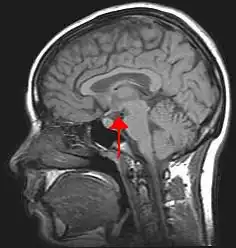

Programmation précoce

Les images par la résonance magnétique (IRM) contemporaine ont procuré un support empirique solide pour la théorie psychologique selon laquelle la programmation émotionnelle est largement définie dans l’enfance, d’autant qu’à l’âge de neuf mois le cerveau a déjà 95 % du volume qu’il aura à l’âge adulte.